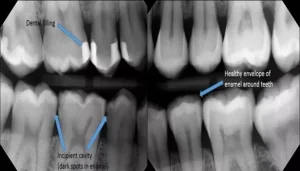

Maintaining optimal oral health is essential not just for a beautiful smile but also for overall well-being. Dental fillings are a common solution for cavities

Dental fillings are a common solution for cavities and tooth decay, providing a protective barrier that restores the tooth’s function and integrity. However, over time,